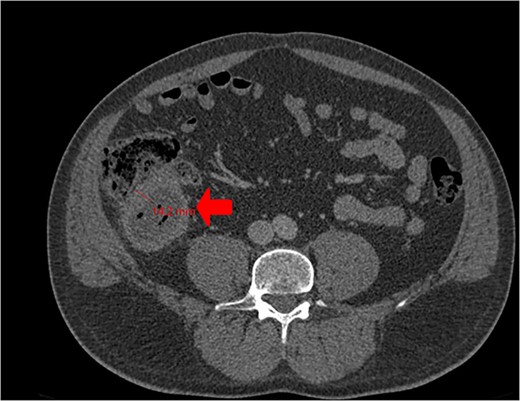

A CT scan showed an oval, 13 × 5.2 cm mass in the right iliac fossa arising from the cecum and running upward, with a thick, edematous wall, fluid, gaseous content, and extensive fat stranding. There was no free fluid and no dilation of bowel, suggesting appendicitis (Figs 1 and 2). Due to these findings, the patient underwent an emergency laparoscopic appendectomy that was converted to open laparotomy. The patient ended up with a right hemicolectomy instead of appendectomy as the appendix could not be separated from the mass, with no separation line between the mass and the cecum. The mass (Fig. 3) measured 10 × 7 × 7 cm and had a thick wall and pyogenic membrane.

Gross specimen showing the terminal ileum, cecum, appendix, and ascending colon. The appendix is visible near the base of the cecum.